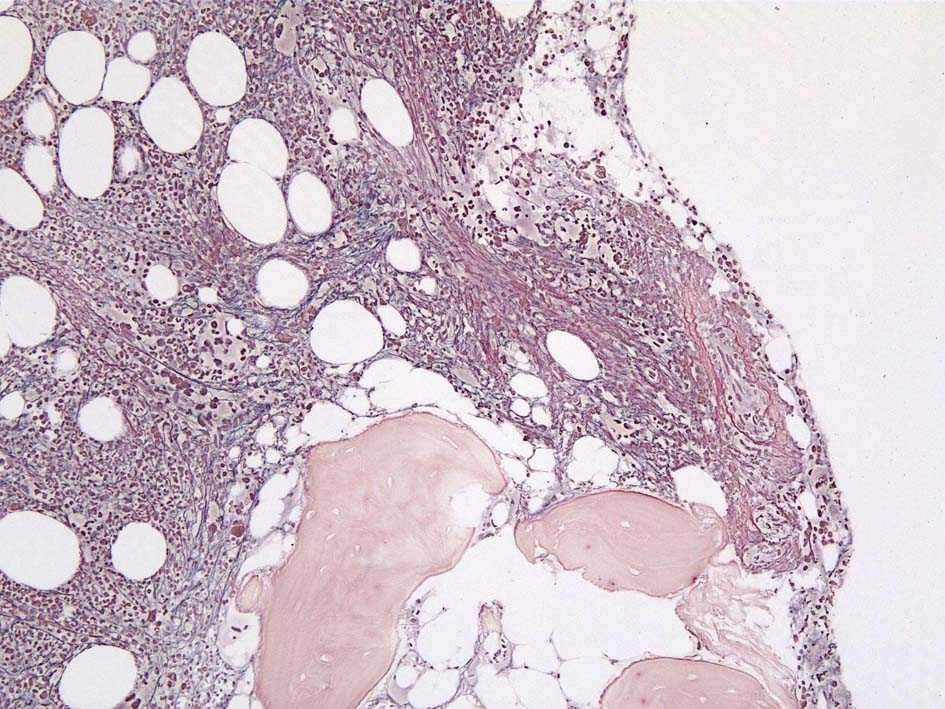

77year-old female. 40歳時polycythemia veraと診断されていた.

[注] この症例は詳細は不明であるが, 過去にPVと診断されているため, PVに伴う二次性のmyelofibrosisの診断になる.

黒染する弾性線維の増生のほか, 赤く染まる膠原線維の増生が確認される. MF-2 fibrosis. 鍍銀染色の核染色をすると膠原線維の赤染がわからなくなるので行わない.